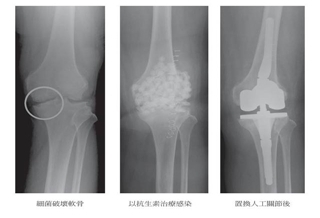

(優活健康網編輯部/綜合整理)近年來也很盛行在關節腔注射玻尿酸(hyal-原意是:像玻璃一樣光亮透明的),以治療「退化」性膝關節炎,玻尿酸是大眾較為熟知的錯誤譯名,正確名稱是透明質酸,它是關節滑液及軟骨的主要成分之一。促進傷口癒合、皺紋填補具有特殊生物活性,能攜帶500倍以上的水分,保水性佳,更具有無毒、低免疫反應、高生物相容及生物可分解以及人體可吸收等特性,早就被廣泛使用在各醫學領域,如:促進傷口癒合、眼睛手術、外科手術防黏劑、美容醫學的皺紋填補、臉部組織的調整等。臨床上所使用的,有由新鮮雞冠提煉精製而成,也有人工合成的。增加潤滑度 避免關節攣縮透明質酸注射至膝關節腔內的作用,就像替生鏽的齒輪加上潤滑油,它可覆蓋於軟骨表面保護軟骨,增加潤滑度,避免關節攣縮,進而增進關節活動範圍,改善日常生活品質,更可減少軟骨持續磨損,延緩置換人工關節的時間。近年來,諸多由藥商贊助的臨床實驗肯定它的卓越療效,病患也因此趨之若鶩。注射透明質酸或生理食鹽水 結果差不多不過,最近丹麥哥本哈根大學老人及免疫風溼科的醫療團隊,在《斯堪地那維亞免疫風溼學》雜誌,發表一篇較客觀的研究報告,值得參考。結論是:在關節腔注射透明質酸或生理食鹽水,結果是差不多的。這個醫療團隊設計了一個嚴謹的臨床試驗,他們以雙盲隨機方式將251位嚴重程度相當的「退化」性膝關節炎患者分成3組,每週施打下列不同製劑,4週共施打4劑:第1組:透明質酸注射劑2毫升(Sodium Hyaluronate);第2組:生理食鹽水20毫升(擴張關節腔,有舒緩症狀的效果);第3組:生理食鹽水2毫升(對照組)。治療後,持續觀察26週。關節腔注射劑有類似安慰劑的效果結果顯示:無論在疼痛的減輕、功能的改善、止痛藥的使用情形,各組治療方式都沒有統計學上的差異。在客觀的疼痛程度計分(VAS, Visual Analogue Scale)及詳細的膝蓋損傷及「退化」性關節炎追蹤量表(Knee Injury and Osteoarthritis Outcome Score, KOOS)計分方面,3組均有相同的改善程度。這間接證明:關節腔注射劑有類似安慰劑的效果,症狀治療的短期效果是如此,長期使用又是如何呢?可否減緩甚至扭轉關節退化呢?可惜,到目前為止,仍無足以採信的相關報告!(本文摘自/自己的膝蓋自己救/時報出版)